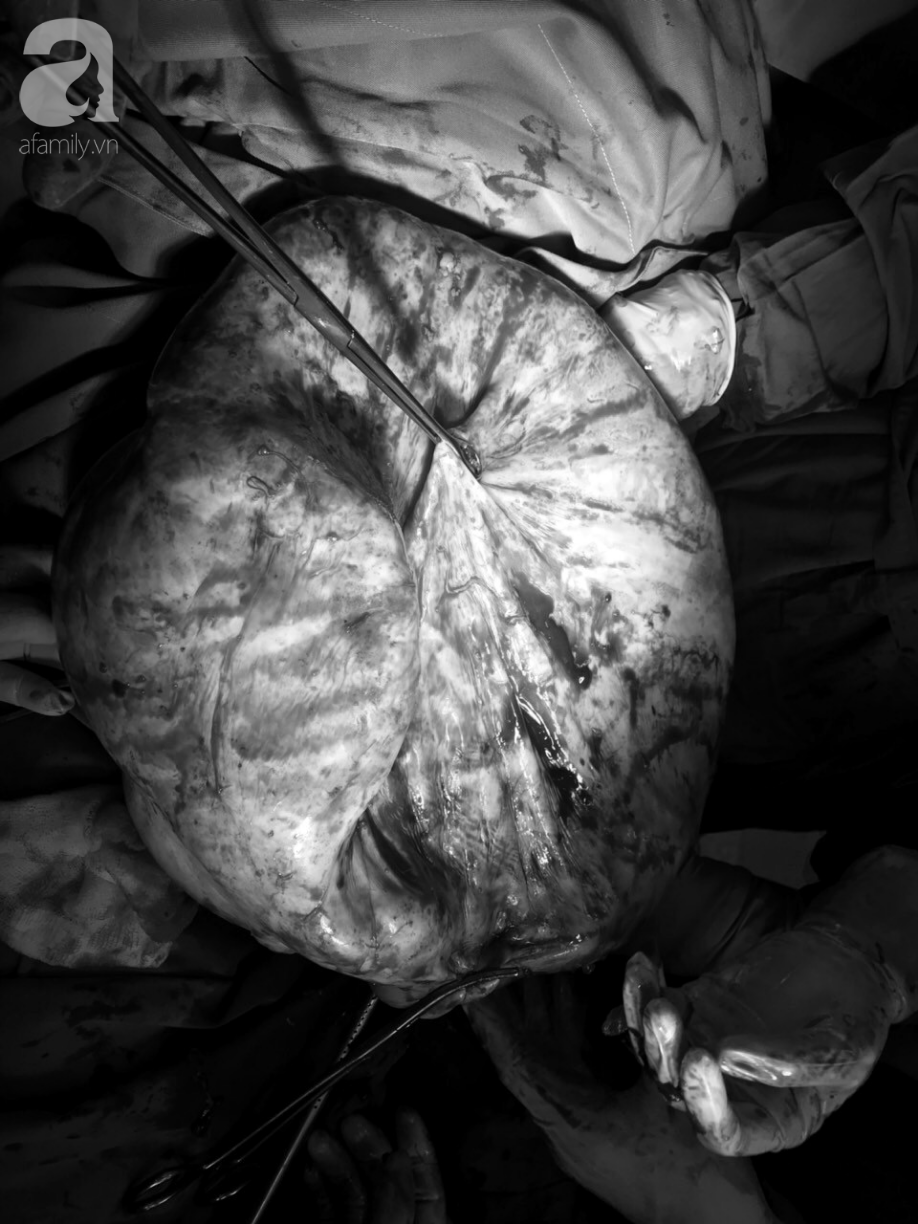

17/07/2018 16:19Thường xuyên ăn đêm, cô gái 20 tuổi nghĩ mình béo bụng chủ quan không đi khám suýt chết vì mang u buồng trứng khổng lồ

Tại BV Hùng Vương, các xét nghiệm một lần nữa khẳng định cô gái mang khối u buồng trứng khổng lồ và chỉ định phẫu thuật.

Ca mổ bắt đầu lúc 7 giờ sáng 13/7 và kéo dài trong hơn một giờ đồng hồ.

Bác sĩ Nguyễn Thị Kim Anh, Trưởng khoa Phụ Ngoại Ung bướu cho biết, khối u to chiếm toàn bộ ổ bụng, dính u thành bụng, dính ruột, đẩy gan phổi lách lên trên gây chèn ép phổi và có tạo dịch trong ổ bụng.

"Khối u xuất phát từ buồng trứng bên trái. Do khối u quá to không thể lấy trọn một lần, chúng tôi đã phải lấy trước khoảng 11 lít phần lỏng trước khi lấy khối đặc nặng 7 kg. Đây cũng là khối u buồng trứng to nhất mà tôi từng gặp", bác sĩ Kim Anh nói.

Dù vậy, mọi khó khăn của ca mổ đã nằm trong tính toán ban đầu. Hai ngày sau khi phẫu thuật, sức khỏe của bệnh nhân đã hồi phục. Do khối u có phần đặc và phần lỏng nên các bác sĩ phải chờ kết quả giải phẫu bệnh. Trong trường hợp khối u ác tính, nếu muốn bảo tồn chức năng sinh sản, bệnh nhân phải tiếp tục được điều trị hóa chất…